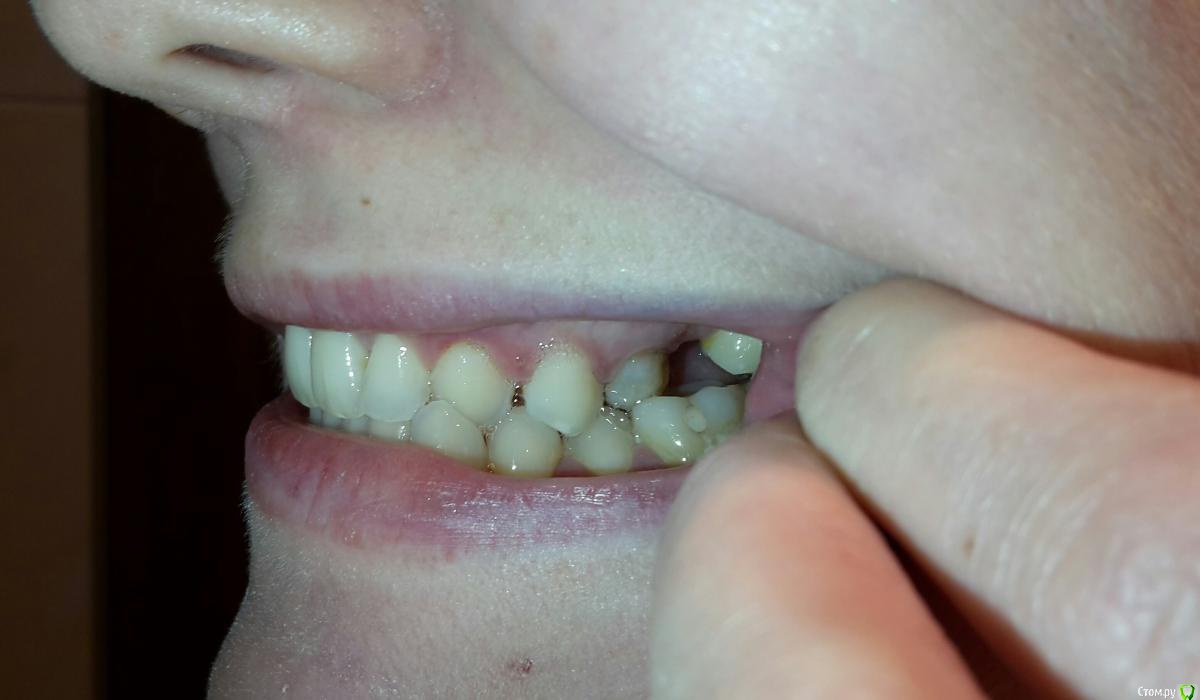

Анастасия Лазарева Опубликовано 15 сентября, 2016 Поделиться Опубликовано 15 сентября, 2016 (изменено) Добрый день, очень прошу совета по своей проблеме. Мне 28 лет. В мае этого года после 2-х часового лечения зубов очень сильно заболела челюсть слева около уха. Чувствую боль также при глотании, иногда отдает в ухо. Больно жевать, особенно жесткую пищу, рот до конца не открывается,максимум на 3-3.5 см. Дальше будто блок. До этого момента в течение многих лет челюсть слева щелкала при зевании и сильном открытии рта, но боли не было, и меня это не беспокоило.Считаю важным отметить, что долгое время я жую все время на правой стороне, тк 6 слева отсутствует с 2005 года. С болью в челюсти обратилась к врачам. Диагноз:двусторонняя болевая мышечно суставная дисфункция внчс..Также отметили неправильный прикус, смещение челюсти, тонус мышц.Предложен план лечения:1. капа. Должна устранить боль в челюсти2. Брекеты для исправления прикуса 3. Имплантация 6 слева.От таких рекомендаций голова кругом... Хотела бы спросить у опытных специалистов прокомментировать мои снимки и фото. Может Вы видите какие-то другие особенности и варианты решения проблемы,которая появилась так внезапно. Заранее очень благодарна за любые рекомендации. Изменено 15 сентября, 2016 пользователем Анастасия Лазарева Ссылка на комментарий